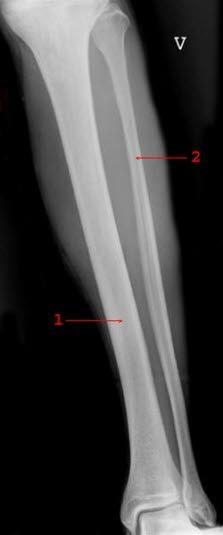

Normalt røntgenbilde av leggDette er en type brudd som oppstår i nedre del av leggen, i skinnebeinet (tibia), hos småbarn. Bruddet skyldes som regel et fall der nedre del av leggen vris.

Slike leggbrudd forekommer oftest hos førskolebarn og presenterer seg gjerne i form av halting. Mest typisk ses bruddet hos barn i alderen 1-3 år som nettopp har begynt å gå (toddler's fracture). I mange tilfeller er det ingen som har observert skaden. Slike brudd kan imidlertid forekomme hos barn helt opp til 6-årsalderen.

Plutselig oppstått halting hos et småbarn gir mistanke om tilstanden. Røntgenbilder vil i de fleste tilfeller bekrefte diagnosen. Andre prøver har liten verdi, men ved usikkerhet om diagnosen - det vil si ingen klare røntgenfunn - vil det være aktuelt å ta en del enkle blodprøver for å utelukke beinbetennelse (osteomyelitt).

Noen ganger er røntgenbildet tilsynelatende normalt. Dersom det likevel mistenkes brudd, anbefales det å gjøre ny røntgenundersøkelse etter 7-10 dager.